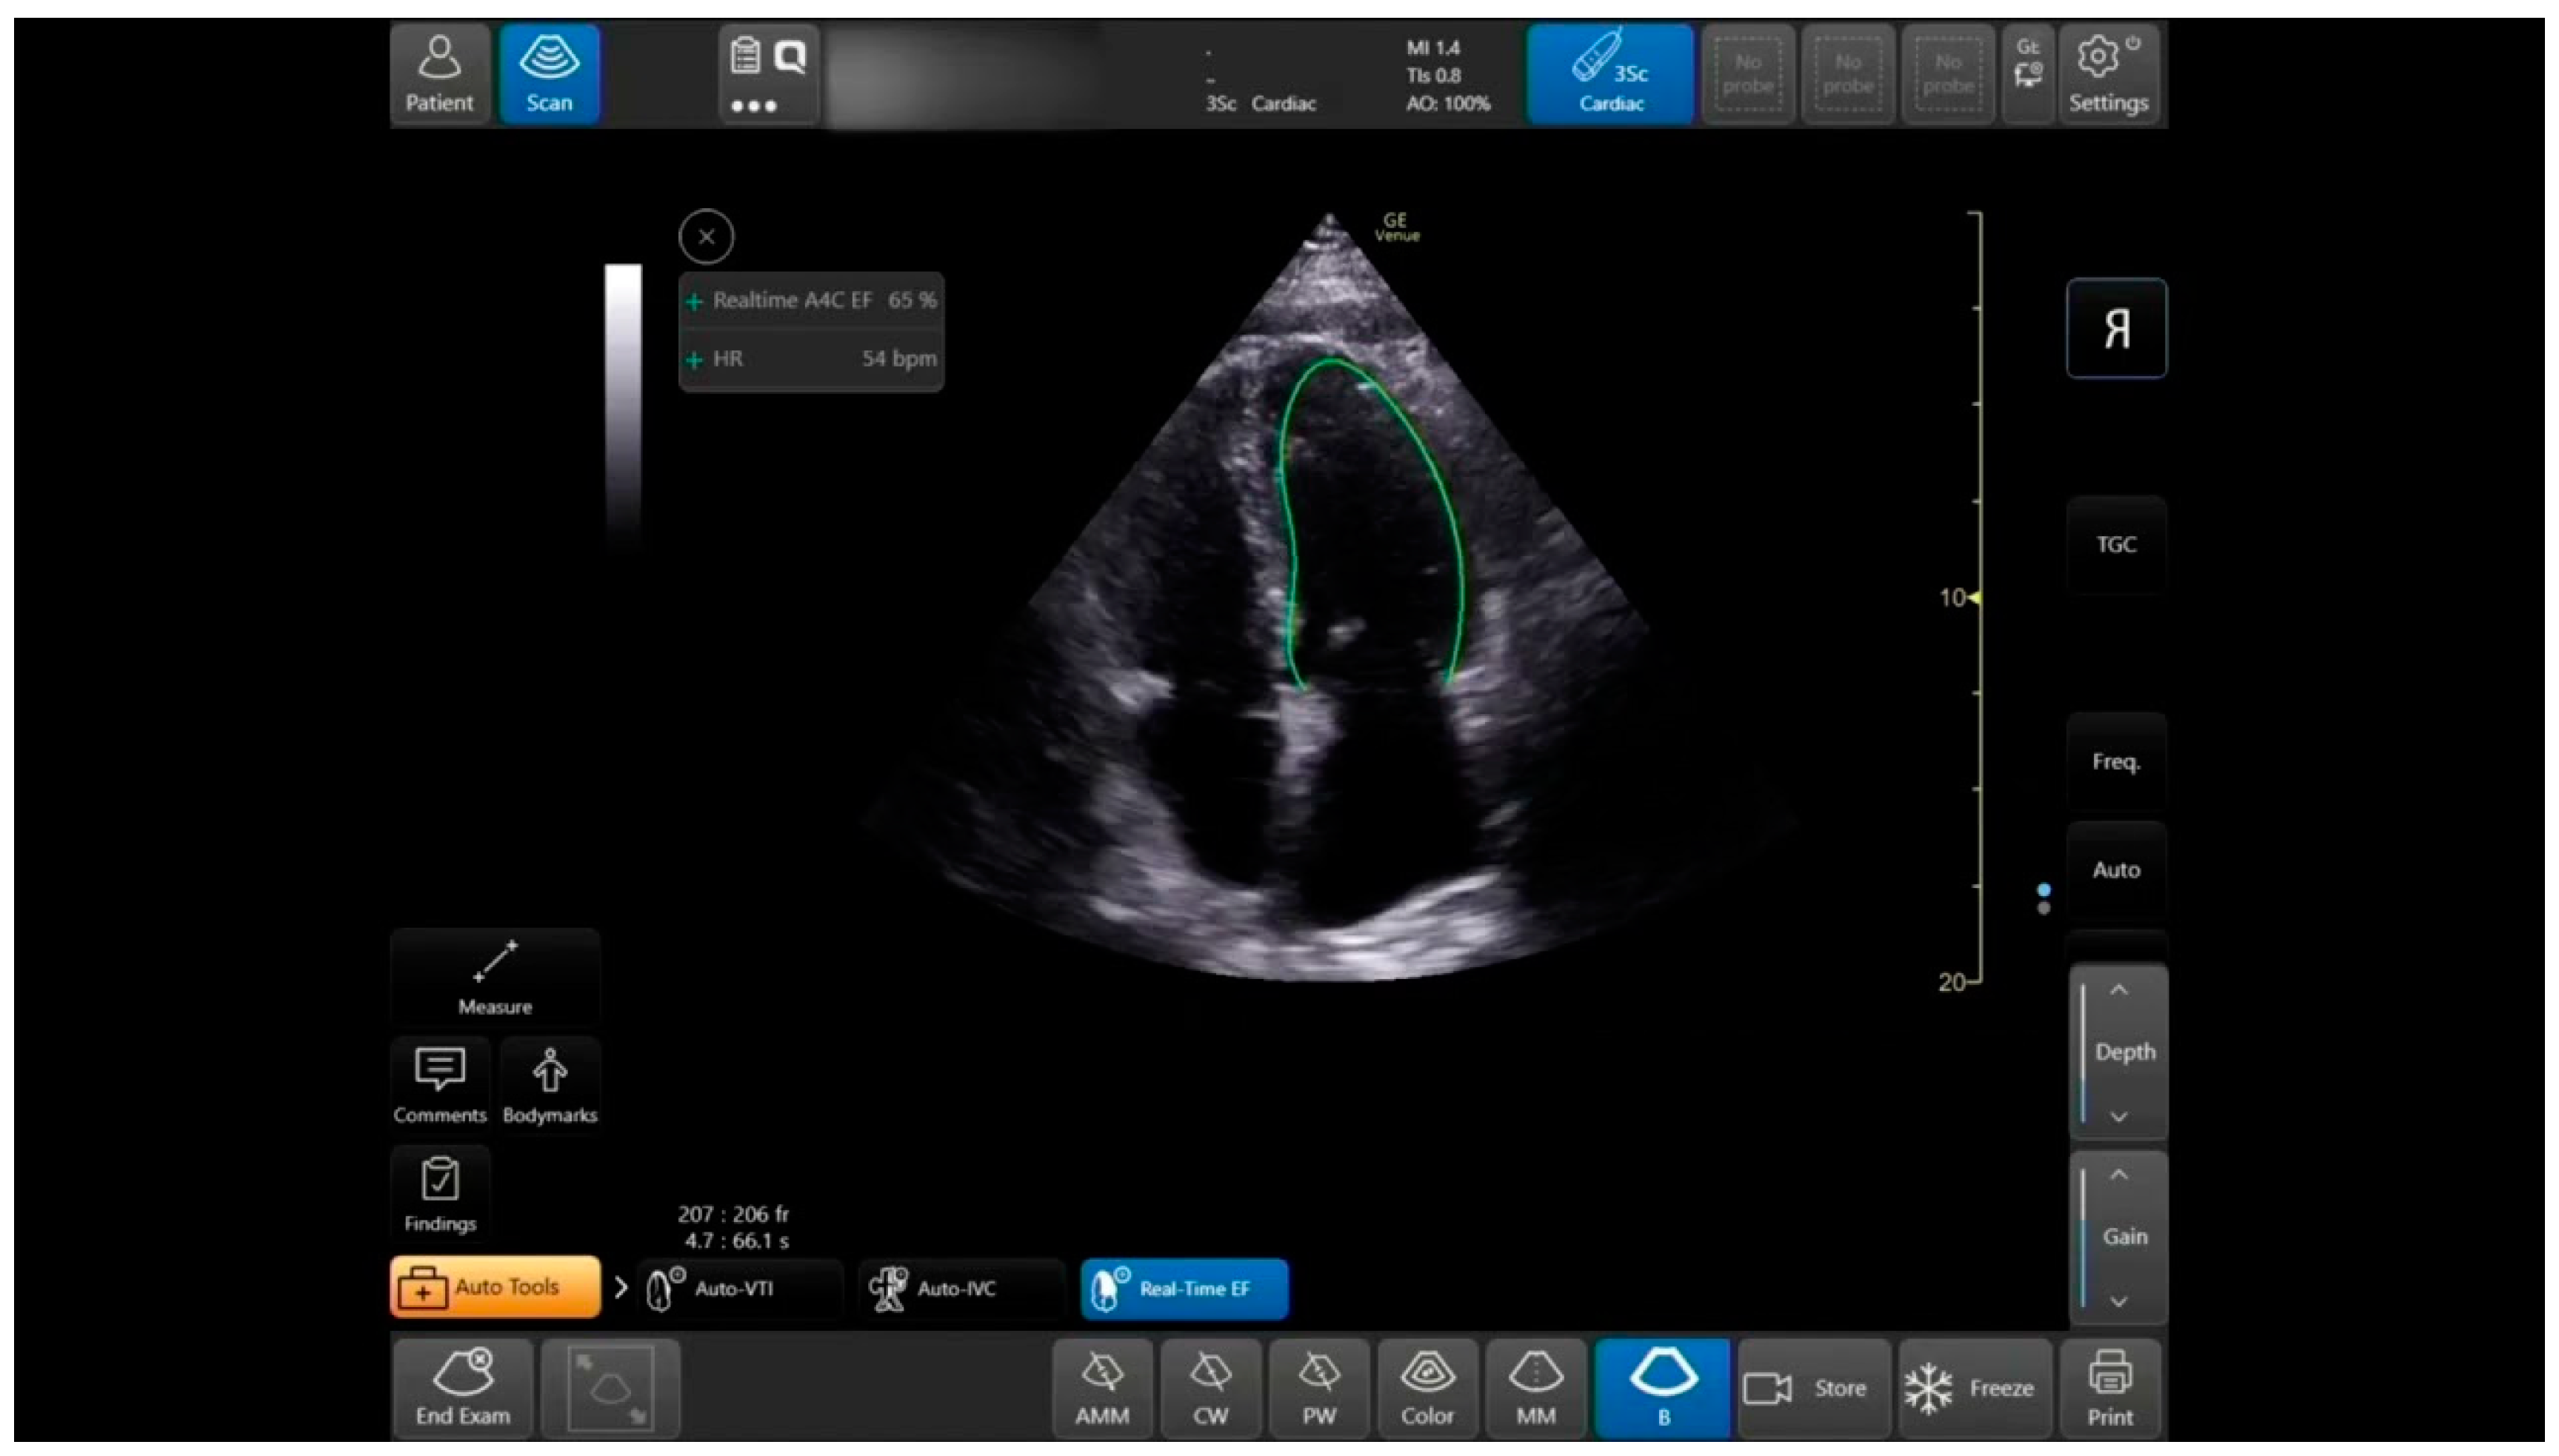

Once the User scans the A4CH view, the Real-Time EF tool identifies the view using Artificial Intelligence (AI) and Machine Learning (ML) algorithms. The semi-automatic tool traces the Ventricle walls per frame and identifies end diastolic and end systolic frames based on the maximal and minimal volumes measured in each heart cycle (Figure 2). Additionally, the tool calculates the image quality based on scanning quality, the tool’s identification of the A4CH view, and the consistency of the EF results. The quality indicator is reflected in the color of the contour. Additionally, if the A4CH view is not detected for more than a few seconds, the tool can indicate the expected location of the LV on the image to the User. Once the User freezes the image, the tool enables quick navigation between the acquired heart cycles and end diastolic and end systolic frames in the last 4 s. This allows for rapid review and selection of the preferable cycle to store and document.

The auto LVEF tool provides two outputs—a score between 0–2 represented to the operator as a colored image quality marker (Red is poor = 0, Yellow is moderate = 1, Green is good = 2), and the EF assessment (presented as a percentage). The expert graded the views blindly, using the same score of 0–2 as the automatic tool for image quality (0—cannot comment on EF, 1—can estimate EF but endocardial border not fully demonstrated, 2—endocardial border well demonstrated), then estimated the EF by the eyeballing technique. We divided the LVEF expert’s assessment into three categories of LV function (preserved, mildly reduced, and reduced EF) as defined in the 2021 ESC Heart Failure guidelines for LVEF: (1) ≥50%, (2) 41–50%, and (3) ≤40%, respectively.

One hundred and thirty-two LVEF clips from 44 patients were acquired from the A4C view. The clips were taken in pairs—a POCUS expert acquired a clip, and then without changing the probe position acquired a second, similar clip. Thus, two groups of paired clips were formed. All clips were interpretable and included in the analysis. Patients were primarily males, with a mean age of 55 ± 19.8 and a mean body mass index (BMI) of 26.8 ± 5.3 (Table 1). Of the first group of clips assessed by the Expert (n = 66), 53 observations were classified as preserved EF (group 1), 11 as moderately reduced EF (group 2), and 2 as severely reduced EF (group 3). High agreement (weighted Cohen’s-Kappa 0.460; p < 0.001) was found between the AI-based automatic EF tool and the Expert’s assessment when the test was conducted on high-quality clips (quality score of 2 as graded by the expert). A much lower agreement was observed in poor-quality clips (Table 2). Higher agreement between the automatic tool and physician EF assessment (weighted Cohen’s-Kappa 0.54; p < 0.001) was observed when LVEF was divided into two groups (1) ≥50% and (2) <50%. The overall agreement between the automatic tool and the physician’s EF assessment was high (weighted Cohen’s-Kappa 0.498; p < 0.001, Table 2). For the image quality agreement, we found a significant difference (p = 0.001, Fishers Exact test value—11.71, α) in the agreement of quality between the physicians’ group and the automatic tools group.

The Left Ventricle Ejection Fraction Automated Measuring Tool was reliable when good cardiac imaging quality is obtained. Most of the study population were patients with preserved LVEF, where the automatic tool was found to be especially reliable. We have found that the overall agreement between the Expert and machine is high (0.498; p < 0.001) and even higher for expert assessment of normal LV. We can confidently confirm that the tool is reliable when the LV is well demonstrated, and its function is normal. Unfortunately, our cohort did not include enough moderate and severe left ventricular systolic function to examine the tool’s accuracy when the heart is not contracting well. Although our findings are limited to normal LV systolic function and should be further studied in different levels of LV function, we believe that novice cardiac ultrasound operators can use this tool for reassurance and confirmation of their EF assessment, especially for normal LV systolic function.

Figure 2. Auto EF tool: in Apical-4-Chamber-View: auto LV outlining in systole and diastole, measurements, and data display.